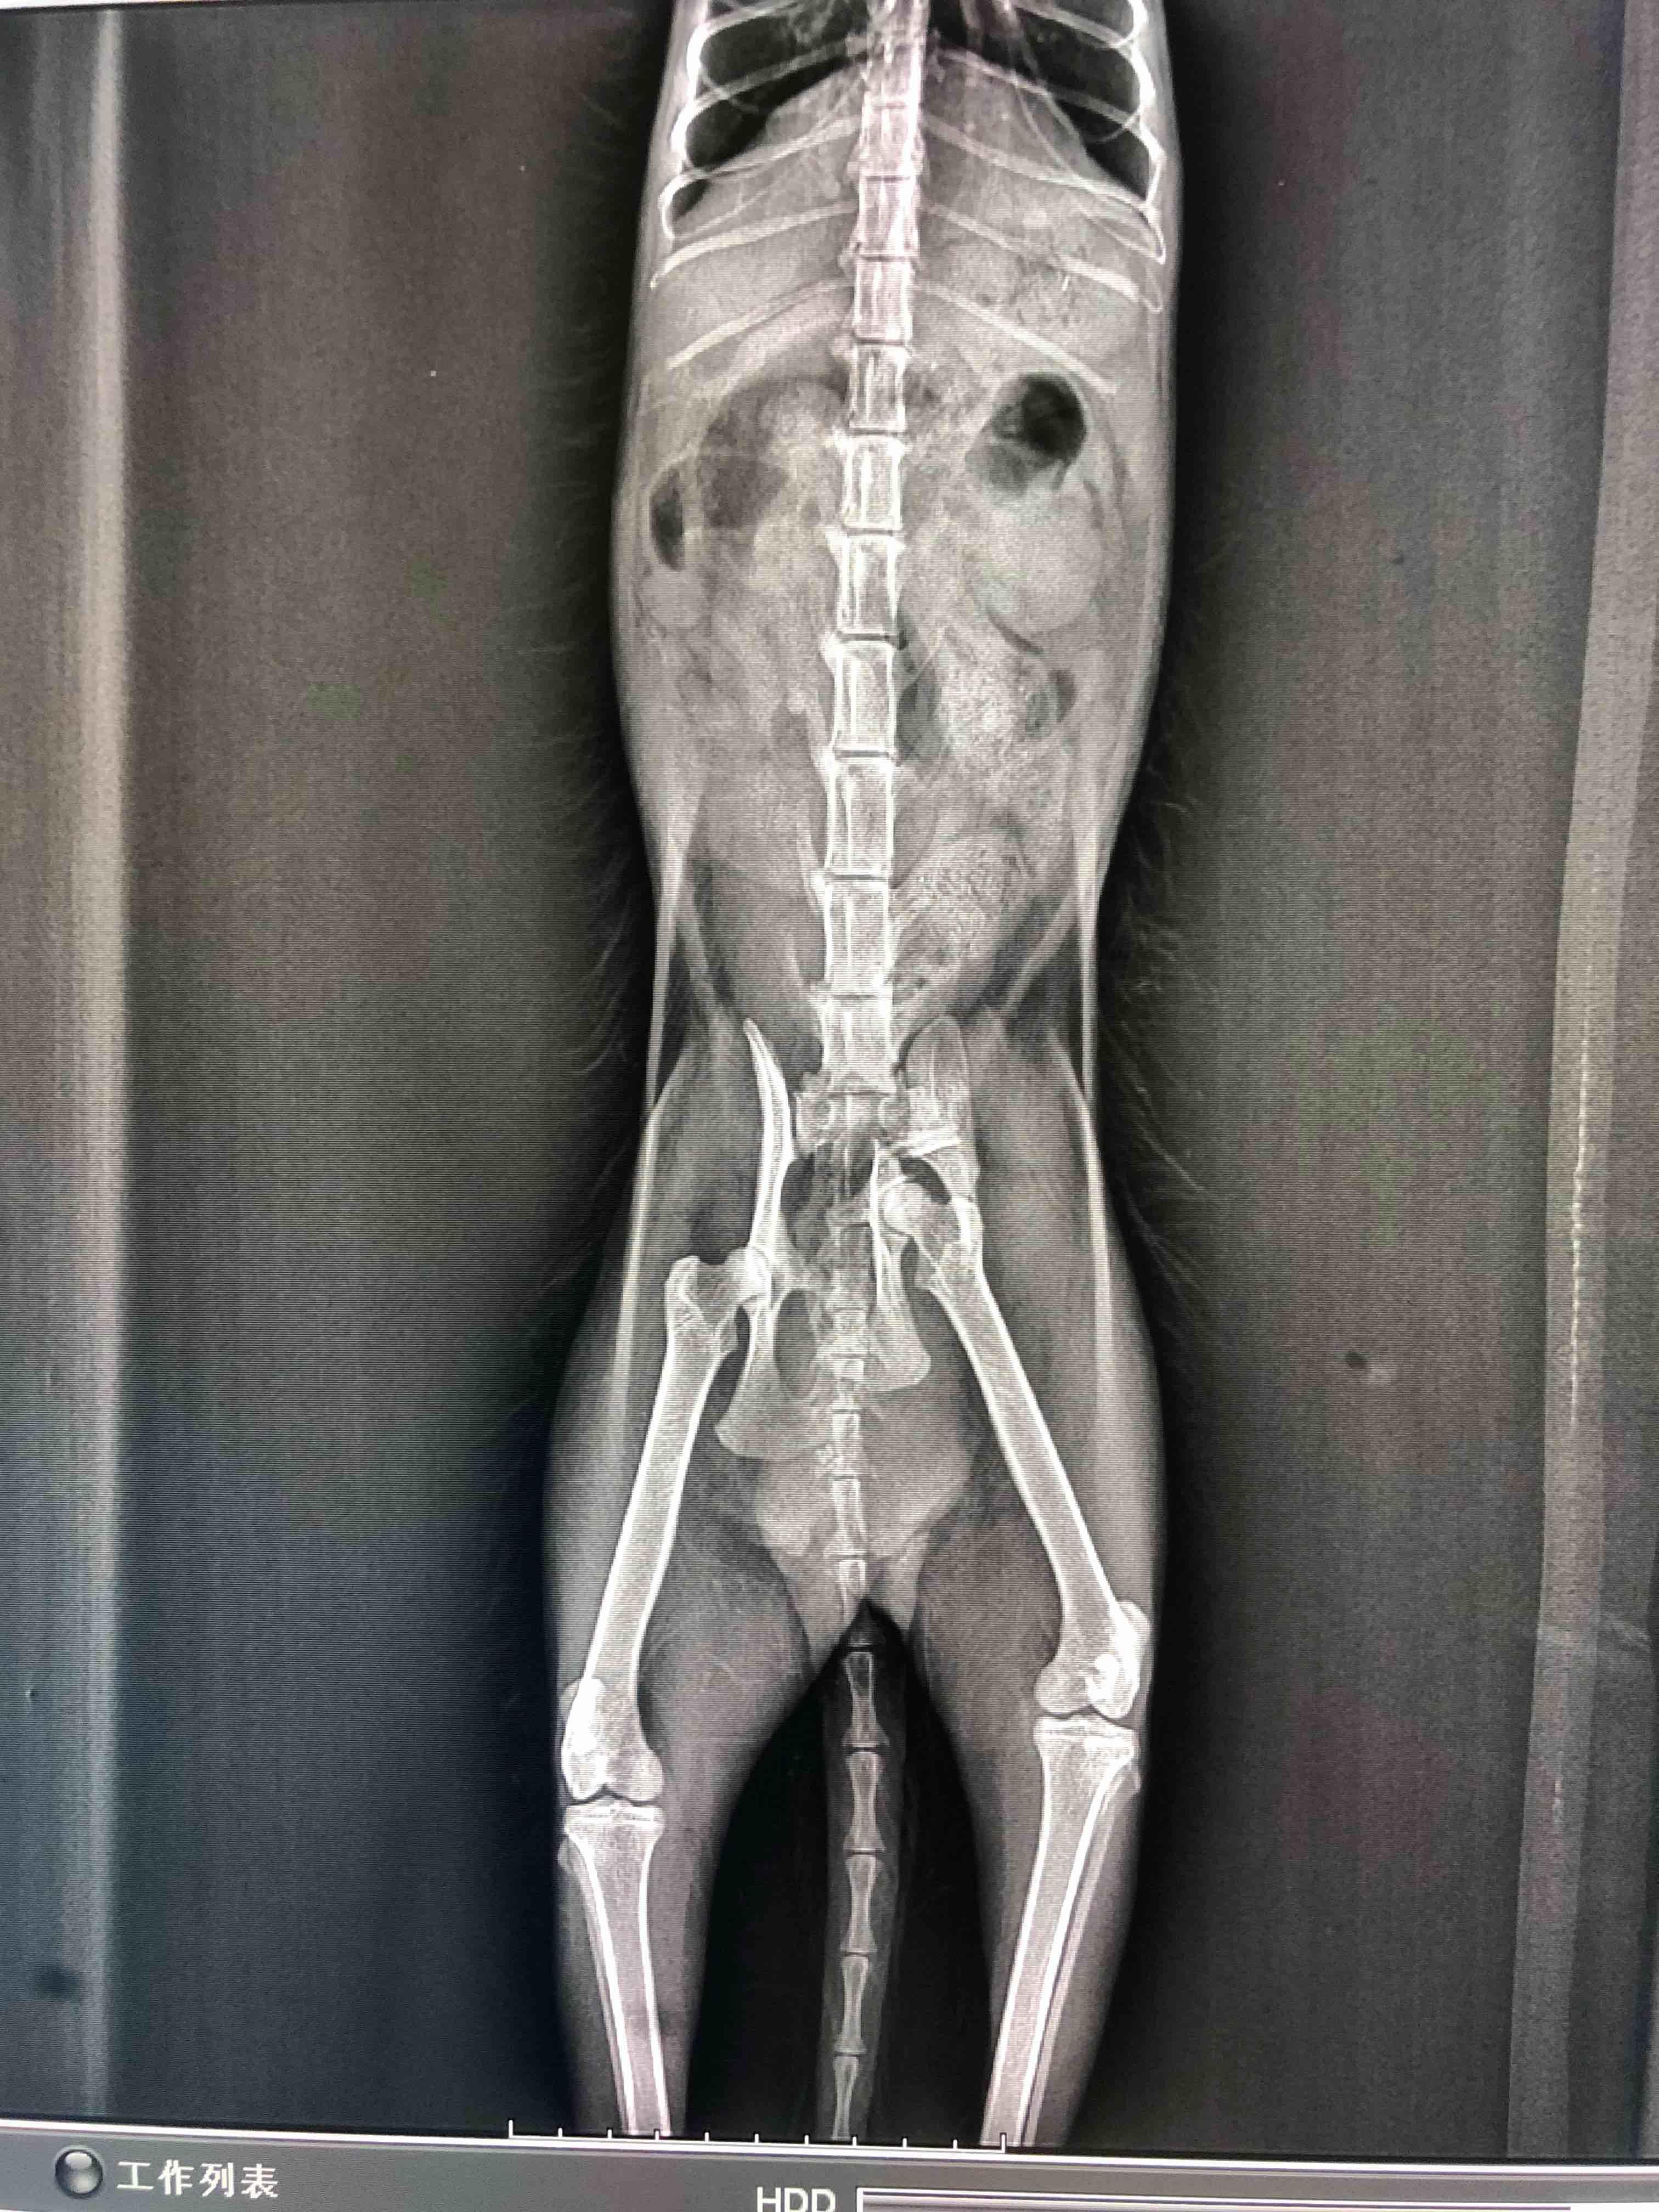

Pet's info: Cat | Mixed Breed | Female | unspayed | 11 months and 30 days old | 5 lbs

I got a cat on street broke her pelvis, I wonder if she can heal on her own or we have to do the operation. With infection and anemia, still stay in hospital.

Poor girl. This is severe break and the pieces are not at all aligned. Unfortunately because the two bones are not aligned properly to heal back together naturally, this likely needs surgical correction. Poor kitty. : ( I recommend discussing with the vet about surgery for this poor kitty to help align the bones. I am not an orthopedic surgeon however, so a consult is needed to discuss if this particular break is repairable surgically or if there are other things that need to be done. Best wishes with your stray kitty Wen. Take care!